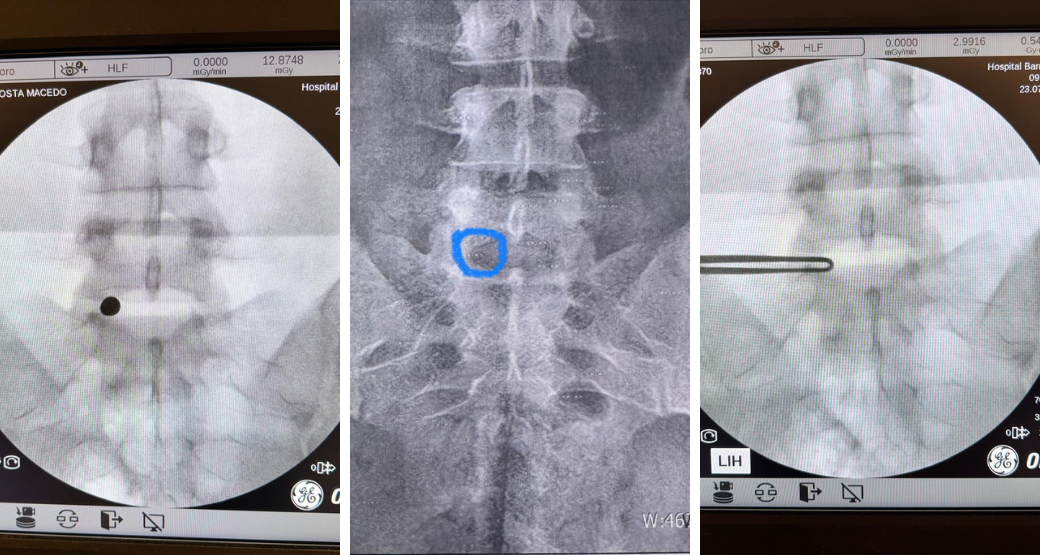

Descompressão endoscópica: Alívio para compressão radicular nas raízes L4 e L5?

“Sem dúvida... Realizamos com sucesso o procedimento em nosso paciente que sofria de dor lombar irradiada para membros inferiores e fraqueza muscular”, comemoram Edward Robert e Renato Bastos, cirurgiões ortopédicos.